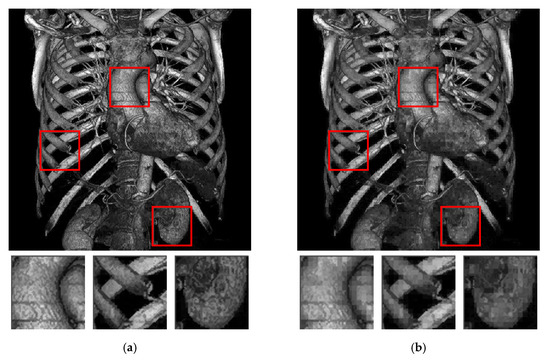

| Figure 6a | Figure 6b | Figure 6c | Figure 6d | Figure 6e | Figure 6f | Figure 6g | Figure 6h | ||

| AMBTC | HPSNR | 52.386 | 53.714 | 52.327 | 56.880 | 51.947 | 55.782 | 51.997 | 53.398 |

| MSSIM | 0.999989 | 0.999993 | 0.999991 | 0.999998 | 0.999988 | 0.999996 | 0.999989 | 0.999992 | |

| [17] | Payload | 47140 | 54040 | 53500 | 113620 | 90940 | 134800 | 86230 | 86755 |

| HPSNR | 45.627 | 47.150 | 46.046 | 50.836 | 45.050 | 48.919 | 45.290 | 46.766 | |

| MSSIM | 0.985399 | 0.989024 | 0.991863 | 0.996137 | 0.991472 | 0.997172 | 0.992645 | 0.992822 | |

| [20] | Payload | 56285 | 64040 | 62915 | 119825 | 100625 | 144560 | 95705 | 95885 |

| HPSNR | 45.305 | 46.676 | 45.621 | 49.429 | 44.617 | 47.689 | 44.828 | 46.192 | |

| MSSIM | 0.983738 | 0.986889 | 0.990008 | 0.990257 | 0.986442 | 0.98905 | 0.988244 | 0.988436 | |

| [22] | Payload | 47140 | 50404 | 53500 | 113560 | 90940 | 134800 | 86230 | 86695 |

| HPSNR | 45.619 | 47.085 | 46.040 | 50.655 | 45.044 | 48.920 | 45.287 | 46.753 | |

| MSSIM | 0.985352 | 0.988626 | 0.99183 | 0.995239 | 0.991359 | 0.997161 | 0.992628 | 0.992788 | |

| Ours | Payload | 101136 | 89360 | 105416 | 133600 | 123408 | 147720 | 122944 | 121792 |

| HPSNR | 52.848 | 53.871 | 52.551 | 57.262 | 53.136 | 56.705 | 53.175 | 54.594 | |